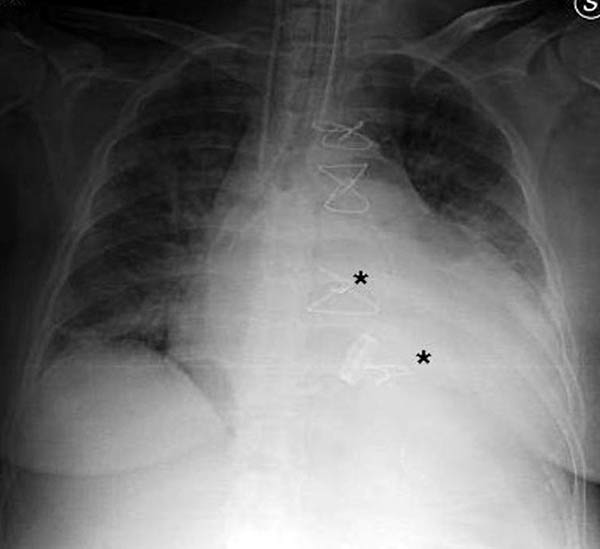

Figure 11. Fourteenth postoperative day image showing sternal wire migration in the caudal sternum segment (*).

Figure 12. Postoperative sternal reconstruction showing sternal fixation with DSS (2 and 3 units in the right and left hemisternum, respectively